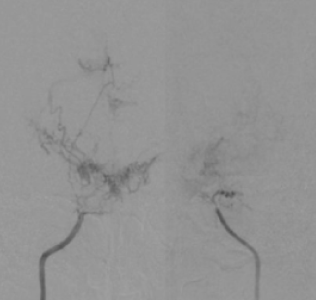

脳動脈瘤、もやもや病などの閉塞性脳血管障害、 脳血管奇形における病態研究を行っています。 特に、若年者の脳卒中の原因として近年増加傾向にある指定難病もやもや病に関しましては 長年の診療経験を踏まえて、遺伝子研究やバイパス周術期病態の解明を中心に先進的研究を推進しています。 もやもや病に対するバイパス手術はガイドラインでも標準治療として推奨されていますが、 術後急性期に局所過灌流(一時的な流れすぎ)や特異な脳虚血病態(watershed shift現象)など、 もやもや病に特徴的な病態を呈することを見出しました。 さらなる治療成績向上を目指して術後急性期の病態解明を脳循環画像やMRIを駆使して推進しています。 また、くも膜下出血の原因として重要な脳動脈瘤に関して高感度MRIを用いた動脈瘤壁イメージング(vessel wall imaging)を 駆使した動脈瘤増大・破裂に関する病態研究を進めています。